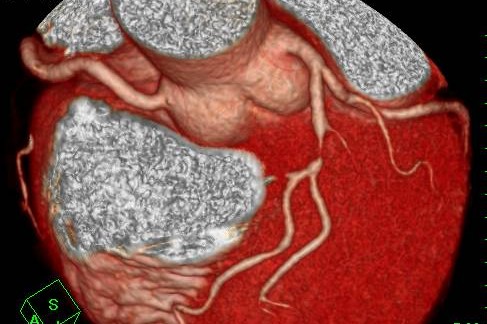

冠動脈CT(冠A-CT)検査について

当院では、冠動脈CT(冠A-CT)検査を行っております。

冠A-CT検査は、心臓の血管(冠動脈)をCTで詳しく調べる検査で、カテーテル検査の前段階として行える、体への負担が比較的少ない検査です。

冠動脈の狭窄(血管の狭くなり)や動脈硬化の状態を画像で確認することができ、自覚症状が出る前の早期の狭心症の発見や、将来の心筋梗塞のリスク評価(予知)に役立ちます。

胸痛・動悸・息切れなどの症状がある方はもちろん、 高血圧・糖尿病・脂質異常症がある方、健康診断で心疾患を指摘された方にも有用な検査です。

気になる症状がある方は、お気軽にご相談ください。

画像検査

X線CT装置で心臓を画像化するという試みは以前からありましたが、検査のためには息止め時間が最短でも40秒と非常に長く、患者さんに大きな負担を与えてきました。導入されているCT装置は、世界で初めて心臓の検査(120mmのスキャン範囲)を8秒の息止め時間で可能にした装置ですので患者さんの負担を大幅に軽減することが可能です。また立体像(3次元画像)として撮影部を360度自由な方向から観察することが可能です。

このX線CTを使用することにより、従来の画像診断装置では困難であった無症状の心血管の狭窄(きょうさく:せまくなっている)を早期に発見したり、カテーテル治療(細い管を体内に挿入し、その先端を風船状に膨らませて心血管の狭窄部分を広げたりする治療)のフォローアップ検査装置として期待されています。